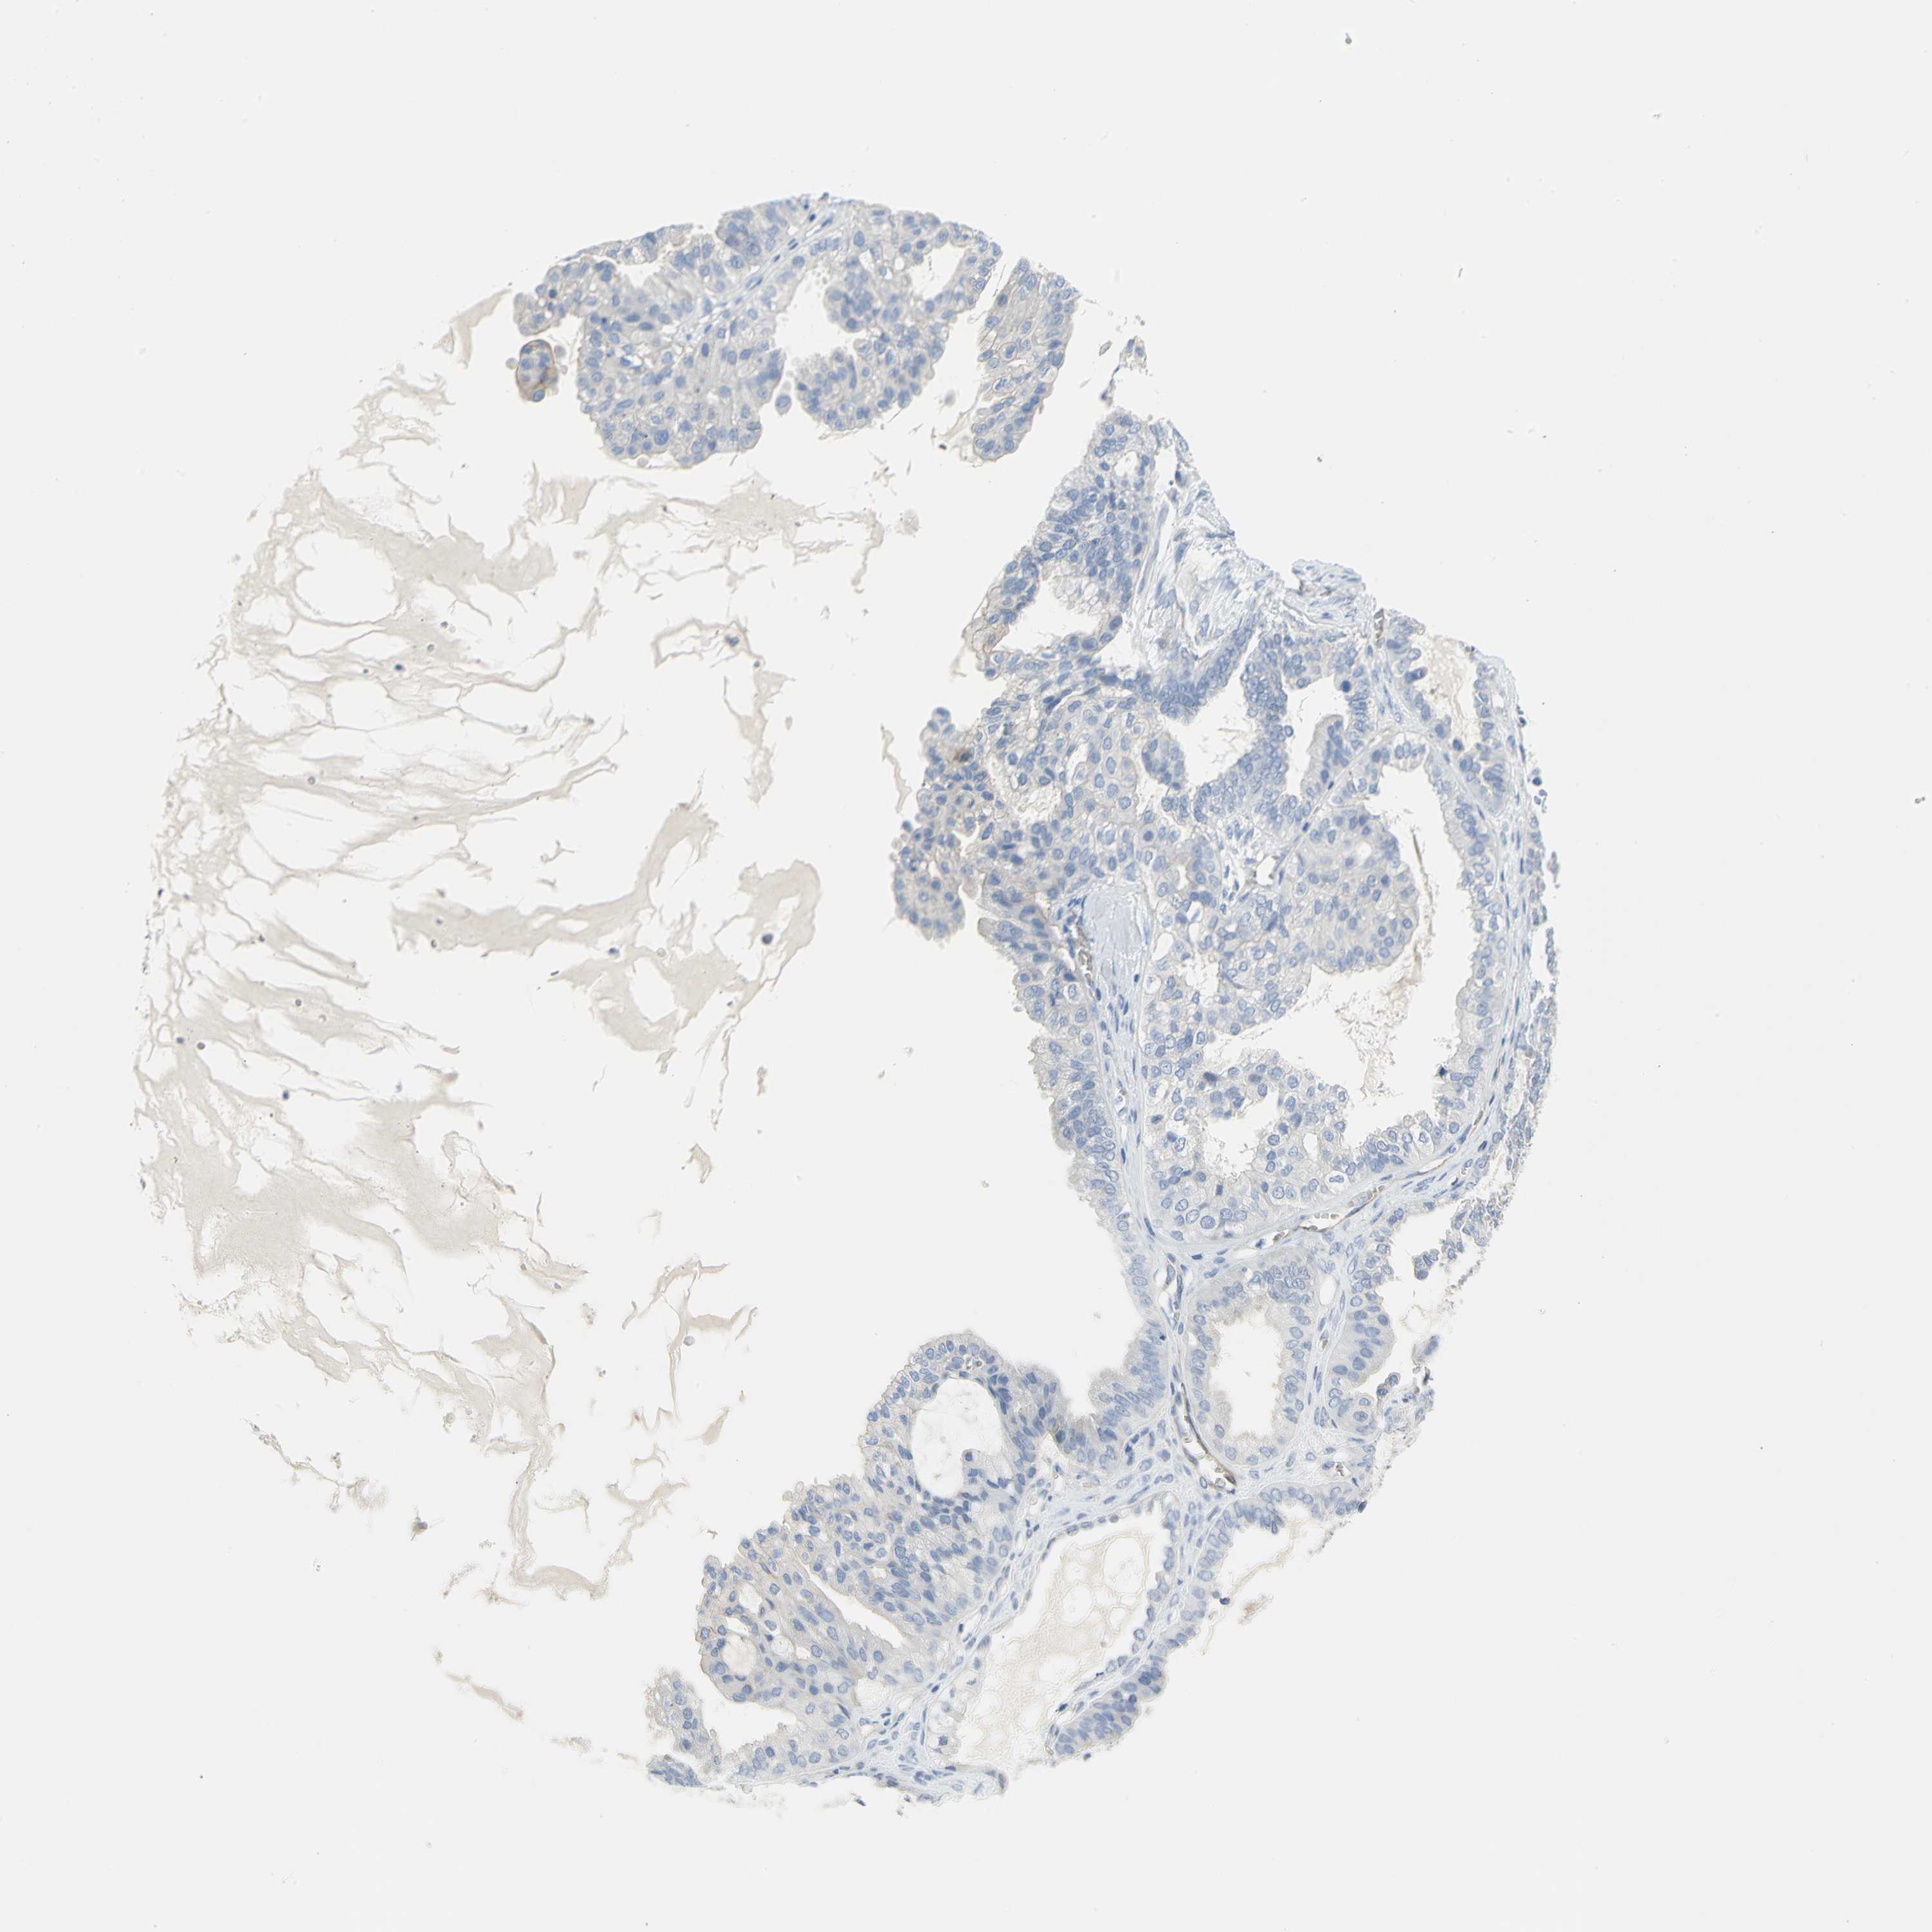

OVARIAN CANCER - Protein expressioni

A mouse-over function shows sample information and annotation data. Click on an image to view it in a full screen mode. Samples can be filtered based on level of antibody staining by selecting one or several of the following categories: high, medium, low and not detected. The assay and annotation is described here.

Note that samples used for immunohistochemistry by the Human Protein Atlas do not correspond to samples in the TCGA dataset.

Antibody stainingi

Antibody staining in the annotated cell types in the current human tissue is reported as not detected, low, medium, or high, based on conventional immunohistochemistry profiling in selected tissues. This score is based on the combination of the staining intensity and fraction of stained cells.

Each image is clickable and will lead to virtual microscopy that enables deeper exploration of all samples and also displays staining intensity scores, fraction scores and subcellular localization as well as patient and tissue information for each sample.

Antibody HPA004747

Antibody HPA004886

Antibody CAB019322

Cystadenocarcinoma, serous, NOS

Carcinoma, endometroid

Carcinoma, NOS

Cystadenocarcinoma, mucinous, NOS